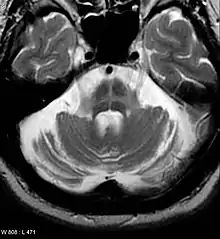

Computed tomography (CT) scans of people with PD usually appear normal.[86] Magnetic resonance imaging has become more accurate in diagnosis of the disease over time, specifically through iron-sensitive T2* and susceptibility weighted imaging sequences at a magnetic field strength of at least 3T, both of which can demonstrate absence of the characteristic 'swallow tail' imaging pattern in the dorsolateral substantia nigra.[87] In a meta-analysis, absence of this pattern was highly sensitive and specific for the disease.[88] A meta-analysis found that neuromelanin-MRI can discriminate individuals with Parkinson's from healthy subjects.[89] Diffusion MRI has shown potential in distinguishing between PD and Parkinson-plus syndromes, as well as between PD motor subtypes,[90] though its diagnostic value is still under investigation.[86] CT and MRI are used to rule out other diseases that can be secondary causes of parkinsonism, most commonly encephalitis and chronic ischemic insults, as well as less-frequent entities such as basal ganglia tumors and hydrocephalus.[86]